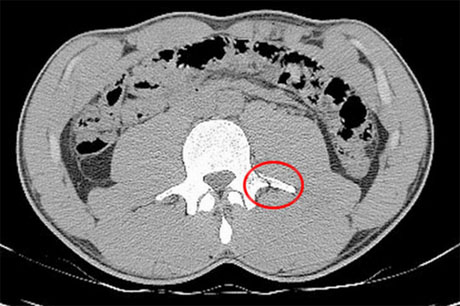

Bola.net - Foto rontgen dari cedera tulang belakang yang dialami oleh Neymar di Piala Dunia 2014 belum lama ini beredar di Internet, menunjukkan betapa seriusnya masalah yang tengah dirasakan oleh bintang Barcelona tersebut.

Foto yang Bolaneters saksikan di atas, sebagaimana dipublikasikan oleh Sport, menunjukkan adanya retak yang dengan amat jelas bisa dilihat di sisi kanan bawah.

Neymar sebelumnya sempat mengklaim bahwa ia bisa saja akan lumpuh seumur hidup andai retak tersebut terjadi beberapa inci lebih rendah.